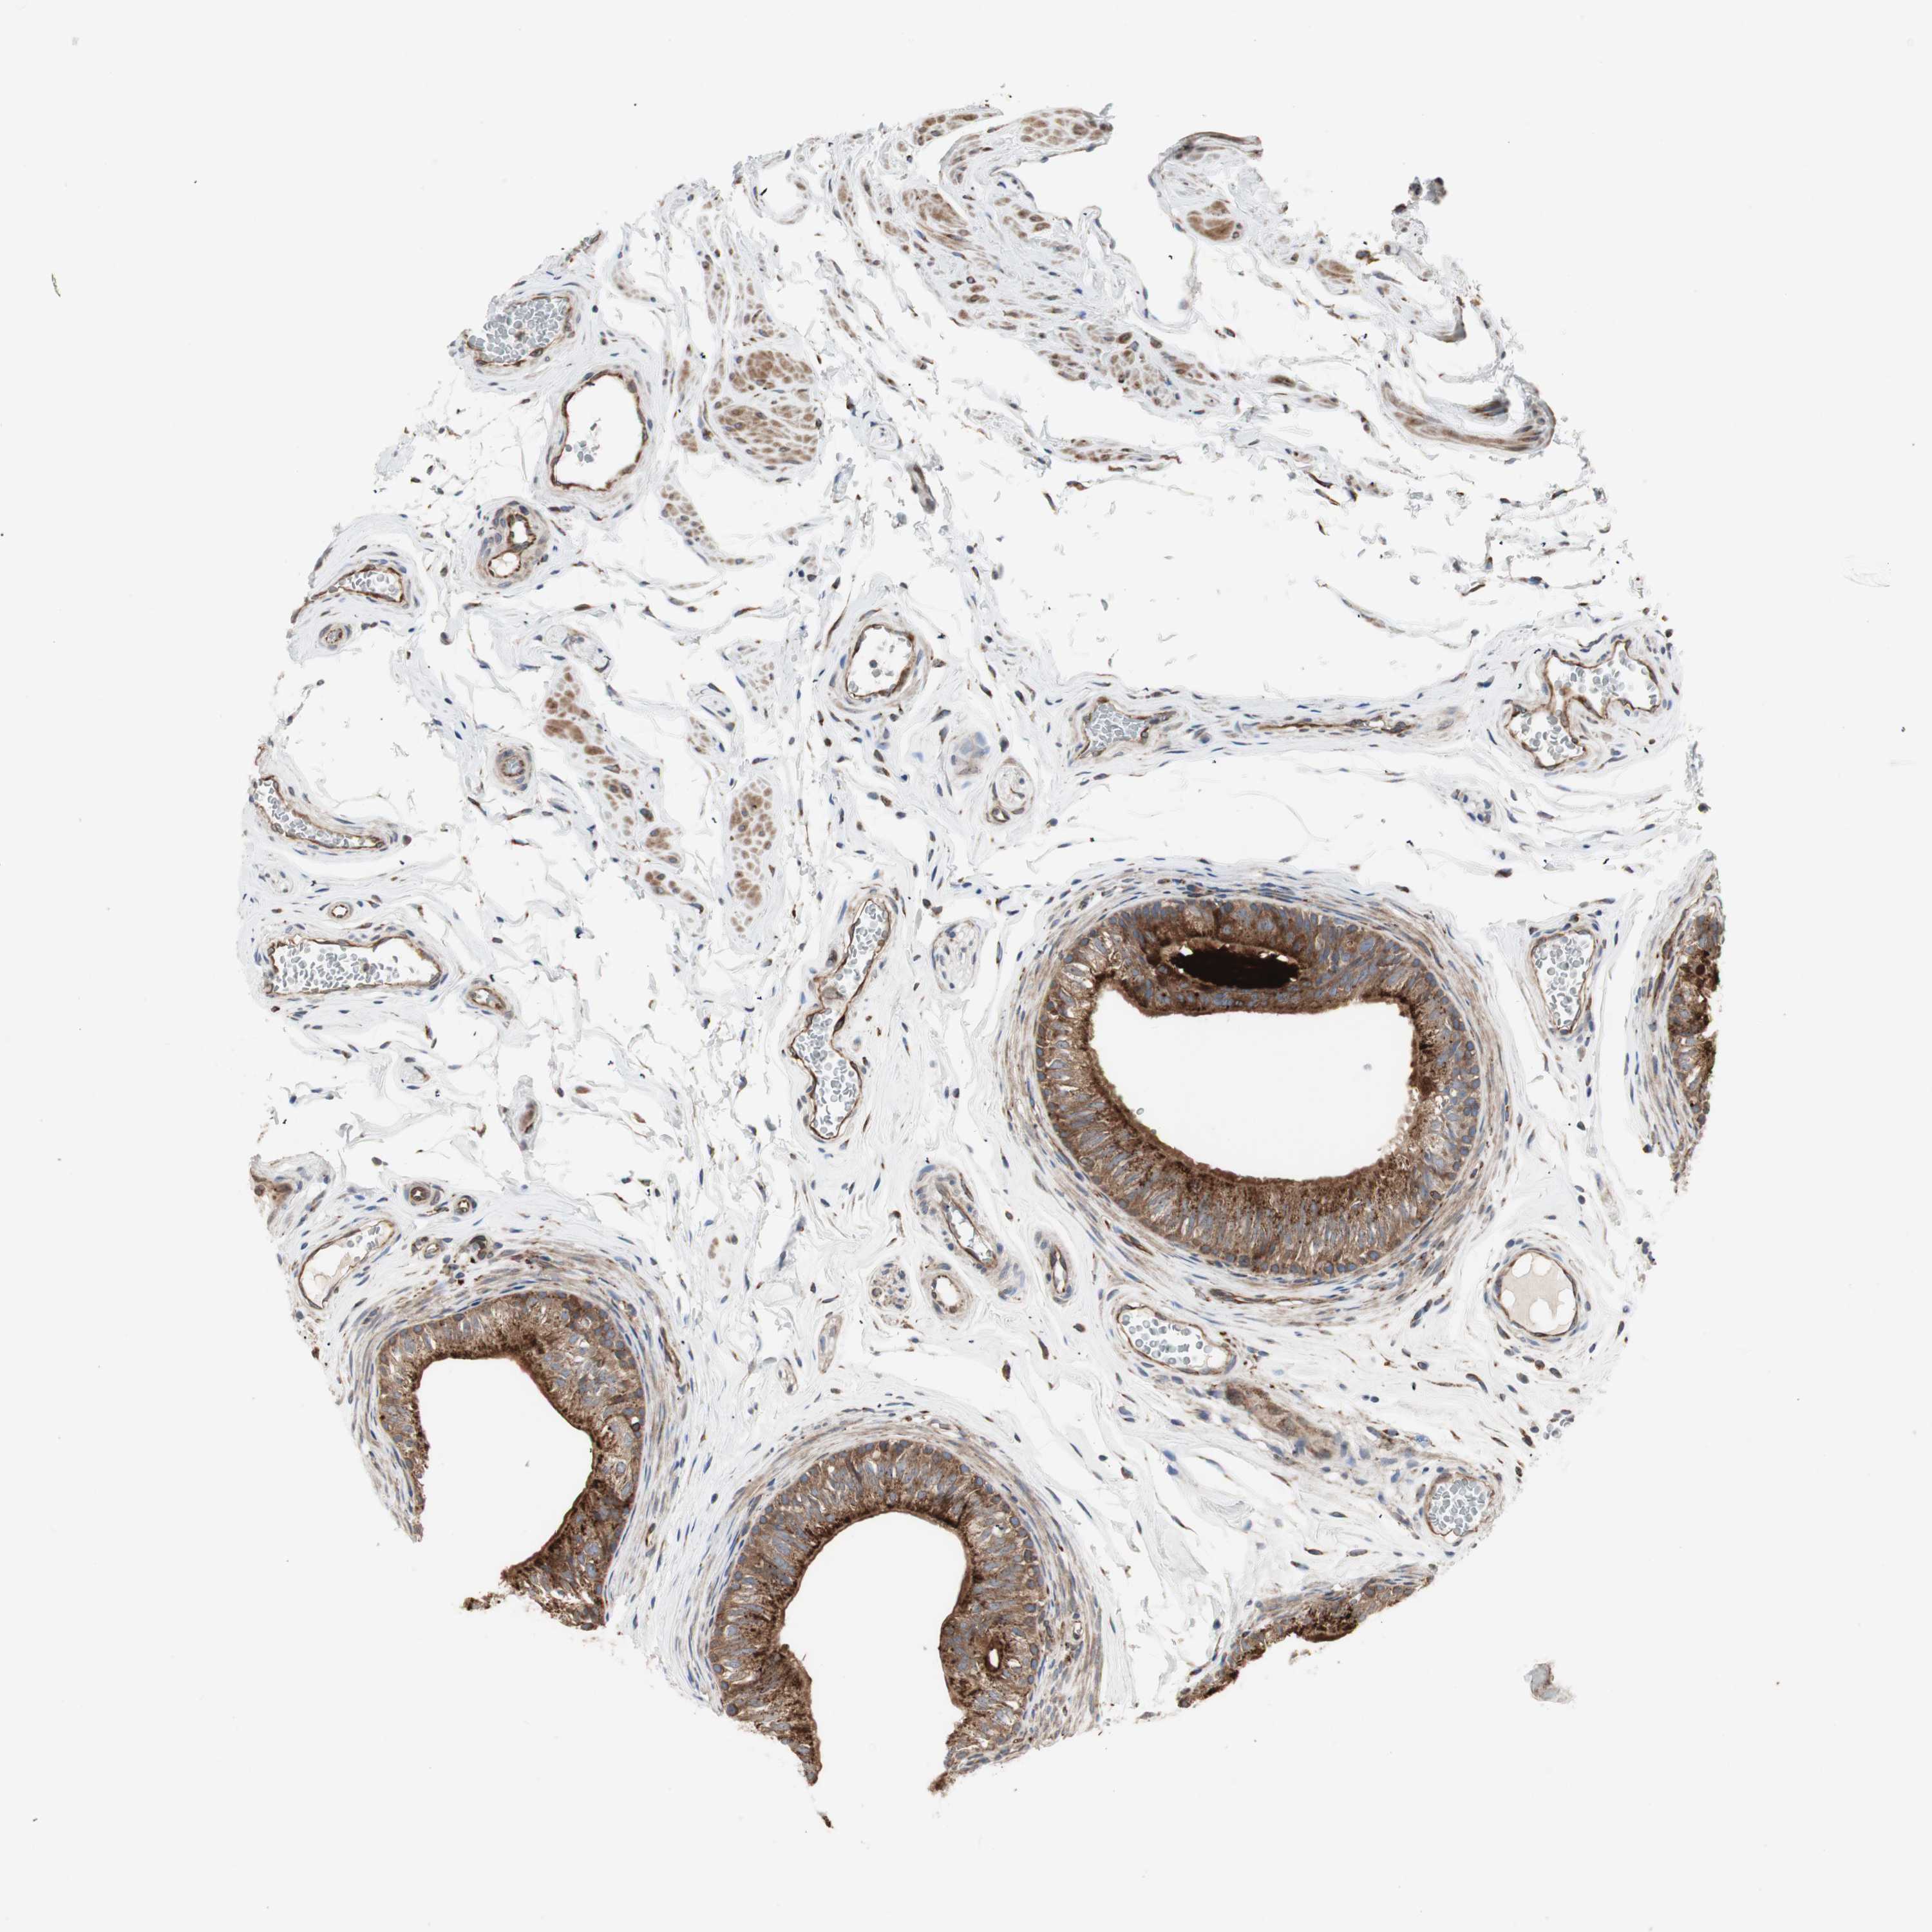

H6PD